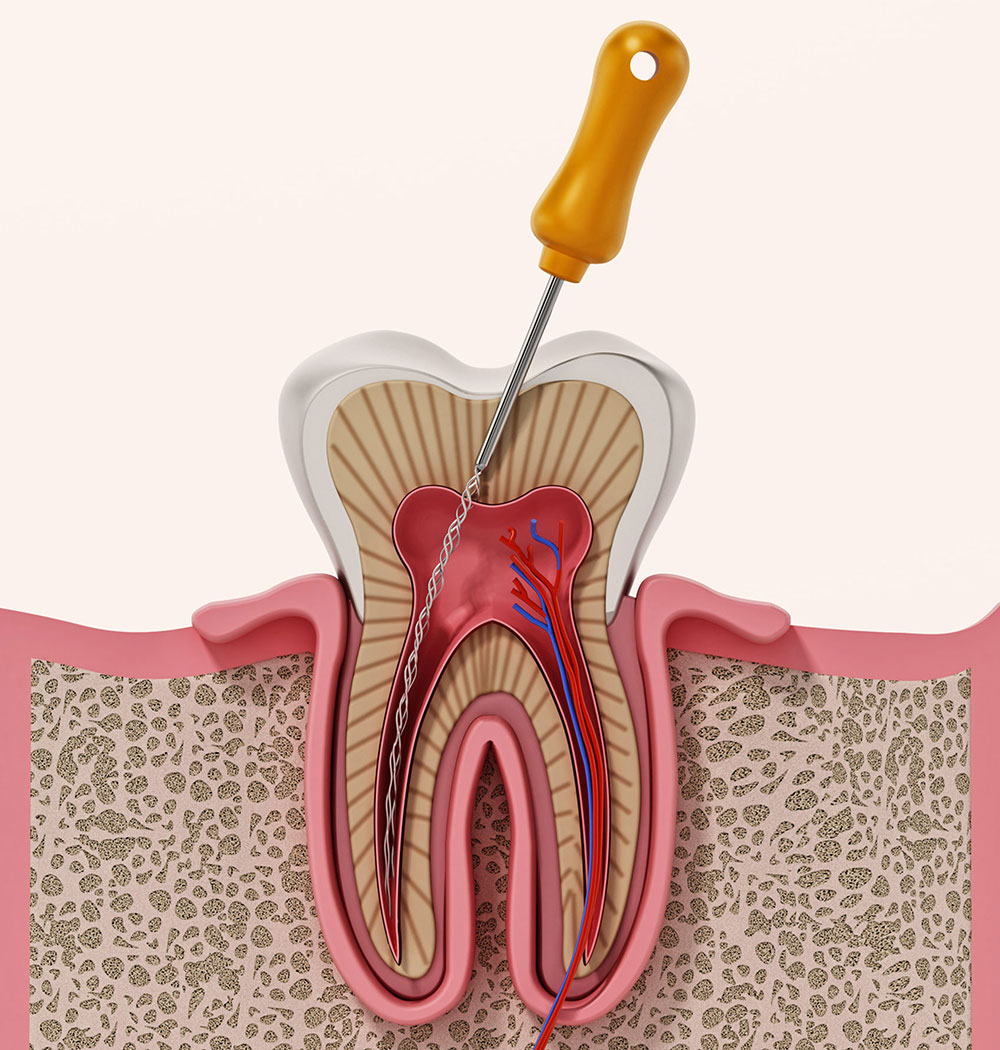

Endodoncia

La endodoncia, comúnmente conocida como tratamiento de conductos, es un procedimiento para eliminar la pulpa dental infectada o dañada y salvar el diente.

El tratamiento de conductos implica varias etapas. Primero se realiza una radiografía para evaluar el estado del diente y planificar el procedimiento. Luego se elimina la pulpa dañada, se limpia y desinfecta el conducto radicular y se rellena y sella el espacio vacío. En algunos casos, se coloca una corona sobre el diente tratado para proporcionar una protección adicional y restaurar su función completa. Este procedimiento es generalmente indoloro y permite salvar el diente afectado.